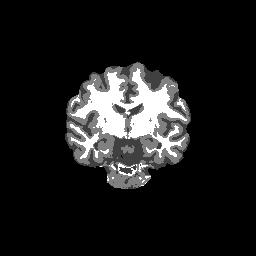

Accuracy is reported as Dice overlaps between a tool's segmentation and the Internet Brain Segmentation Repository (IBSR) manual segmentation for each of the 18 IBSR subjects. The inter-tool comparison (on the left below) shows the median Dice coefficient for each tissue class. The overlaps for FSL (from which the median values are drawn) are shown in the plot on the right.

Overlap coefficients for each tissue class are shown here for each IBSR subject. Select a subject below to see the FSL results compared to other tools.